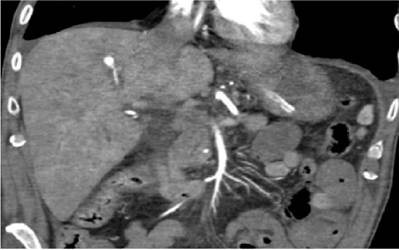

Based on these findings, CT-angiography was performed (Figure 1). It identified an aneurysm of a segmental branch of the right hepatic artery which had fusiform content suggestive of a biliary intraluminal hematoma.